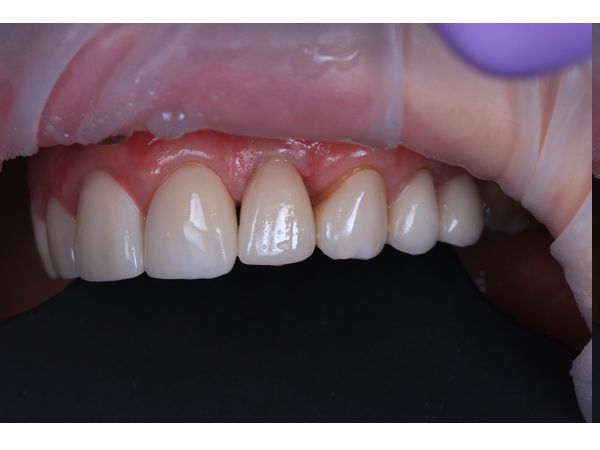

Через 3 месяца после интеграции импланта временную коронку заменили на постоянную циркониевую коронку.

По результатам повторной компьютерной номограммы, вестибулярная кортикальная пластинка и объём костной ткани восстановились. Пациентка ни на что не жаловалась. Внешний вид её полностью устроил.